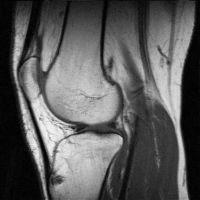

Kernspinaufname eines Knigelenks

Di Vekselvirkung der Atomkerne mit irer Umgebung

erlaubt di Unterzuxung xemicer Strukturen

(Kernspinrezonantscpektroskopi)

bis hin tsu bildgebenden Ferfaren inn der Meditsin

(Kernspintomografi).

Fundctelle der

Kernspinaufname